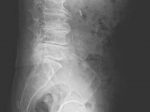

腰痛疾患の場合、レントゲン写真やMRI画像により何らかの椎間板障害が確認できた時の治療の進め方になります。

治療に当たっては、レントゲン写真は必須であり、現在の椎間板障害レベルを把握する意味で所見時には非常に重要な検査の一つに当たります。

椎間板障害には、それぞれグレードレベルがあり、どのくらいのステージレベルにあるかをまず診断する必要があります。

腰痛のほとんどは数週間で自然に解消しますが、もし改善が見られない人は、レントゲン写真で画像診断または臨床検査が必要な時があるため、一度腰椎を確認する必要があります。

その他X線やMRIなどの画像検査も必要になる場合があります。